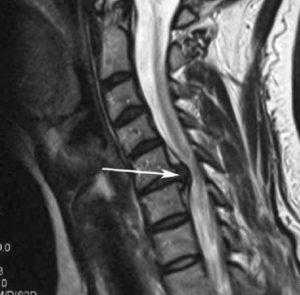

Стеноз шейного отдела вследствие грыжевого выпячивания.

- МРТ позвоночника. Определяется снижение интенсивности сигнала на Т1-взвешенных снимках и его повышение на Т2-взвешенных изображениях, деформация межпозвоночных дисков, структурные изменения тел позвонков. Чувствительность магнитно-резонансной томографии достигает 96%, точность - 94%, поэтому ее считают «золотым стандартом» диагностики.